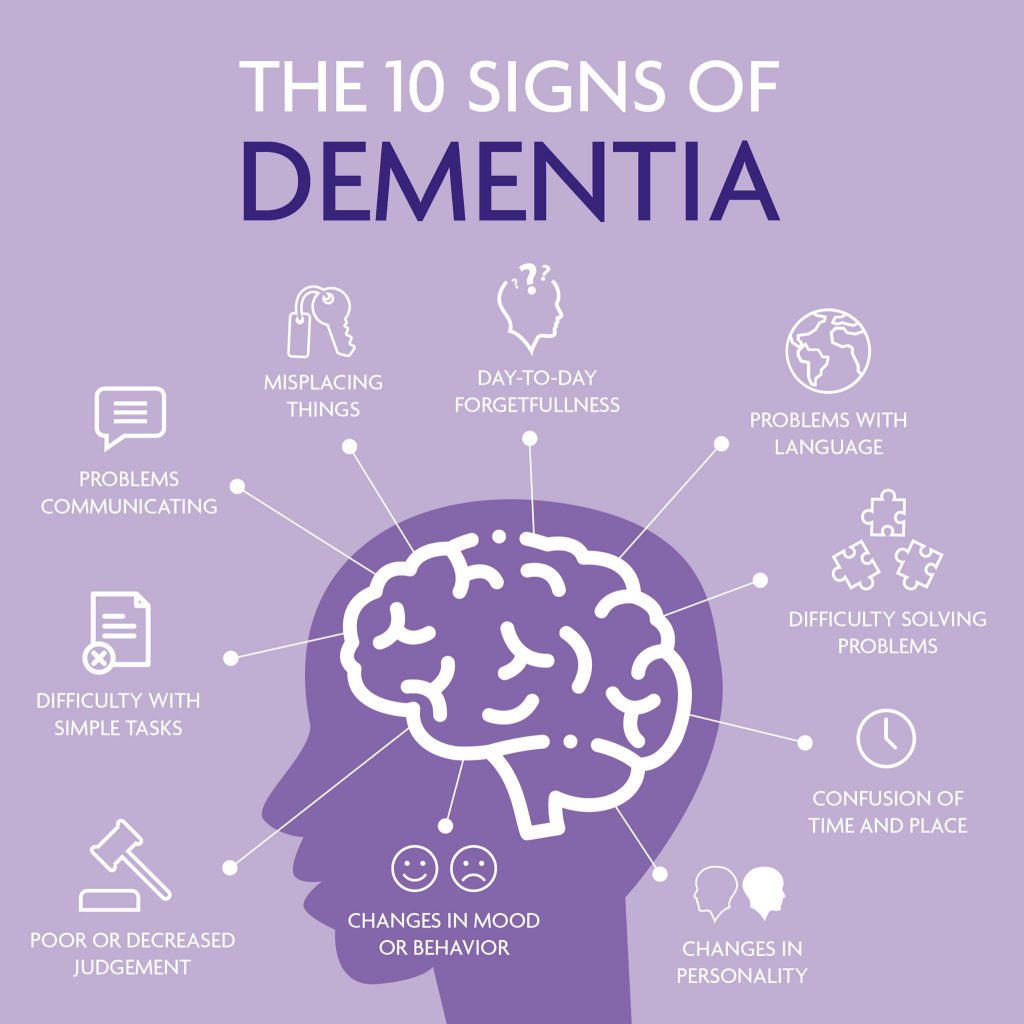

Dementia

Dementia 101: Know the Different Types of Dementia

Dementia is an umbrella term. It describes the symptoms that occur when …